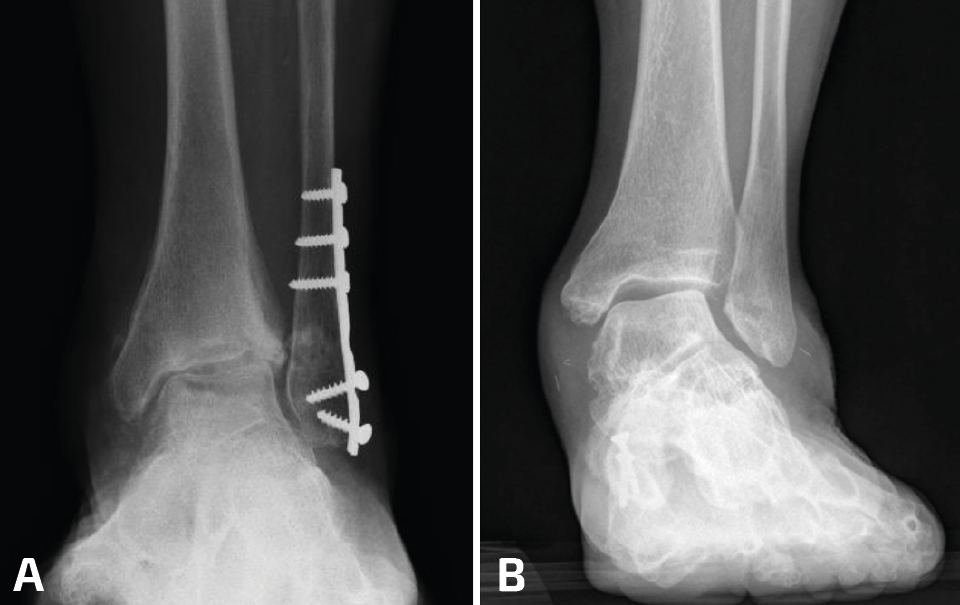

• Traumática: es la causa de hasta el 80% de las artrosis de tobillo en general y también la más frecuente de aquellas en valgo(1,2). En el caso de las artrosis asimétricas traumáticas en valgo la causa más frecuente son aquellas fracturas con compromiso articular con impactación del plafón tibial lateral (Figura 1A).

• Pie plano valgo del adulto (PPVA) (Figura 1B). La deformidad en PPVA es otra causa de artrosis asimétrica importante. No en vano la clasificación de Myerson y Bluman del PPVA tiene un grado específico para este escenario: el PPVA de grado IV(3).

- Articulación estable y paralela tibiotalar (TT). De esta forma descargamos el área enferma de la superficie articular haciendo pasar la carga de la “concavidad a la convexidad de la deformidad” (Figura 1).